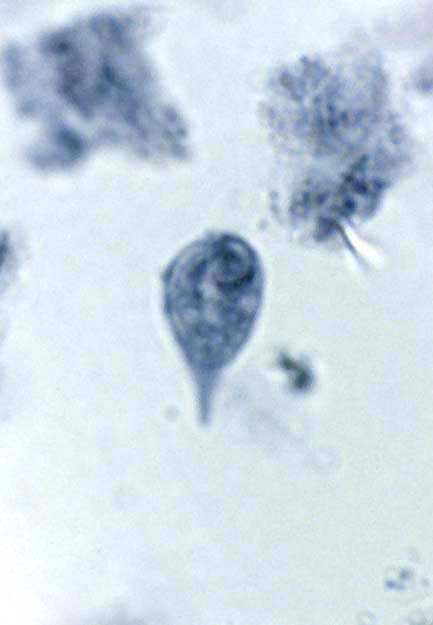

Chilomastix Mesnili Cyst And Trophozoite

4 Chilomastix Mesnili Royalty-Free Images, Stock Photos & Pictures ... CDC - DPDx - Chilomastix mesnili CDC - DPDx - Chilomastix mesnili Chilomastix - an overview | ScienceDirect Topics CDC - DPDx - Chilomastix mesnili Chilomastix Mesnili Cyst And Trophozoite